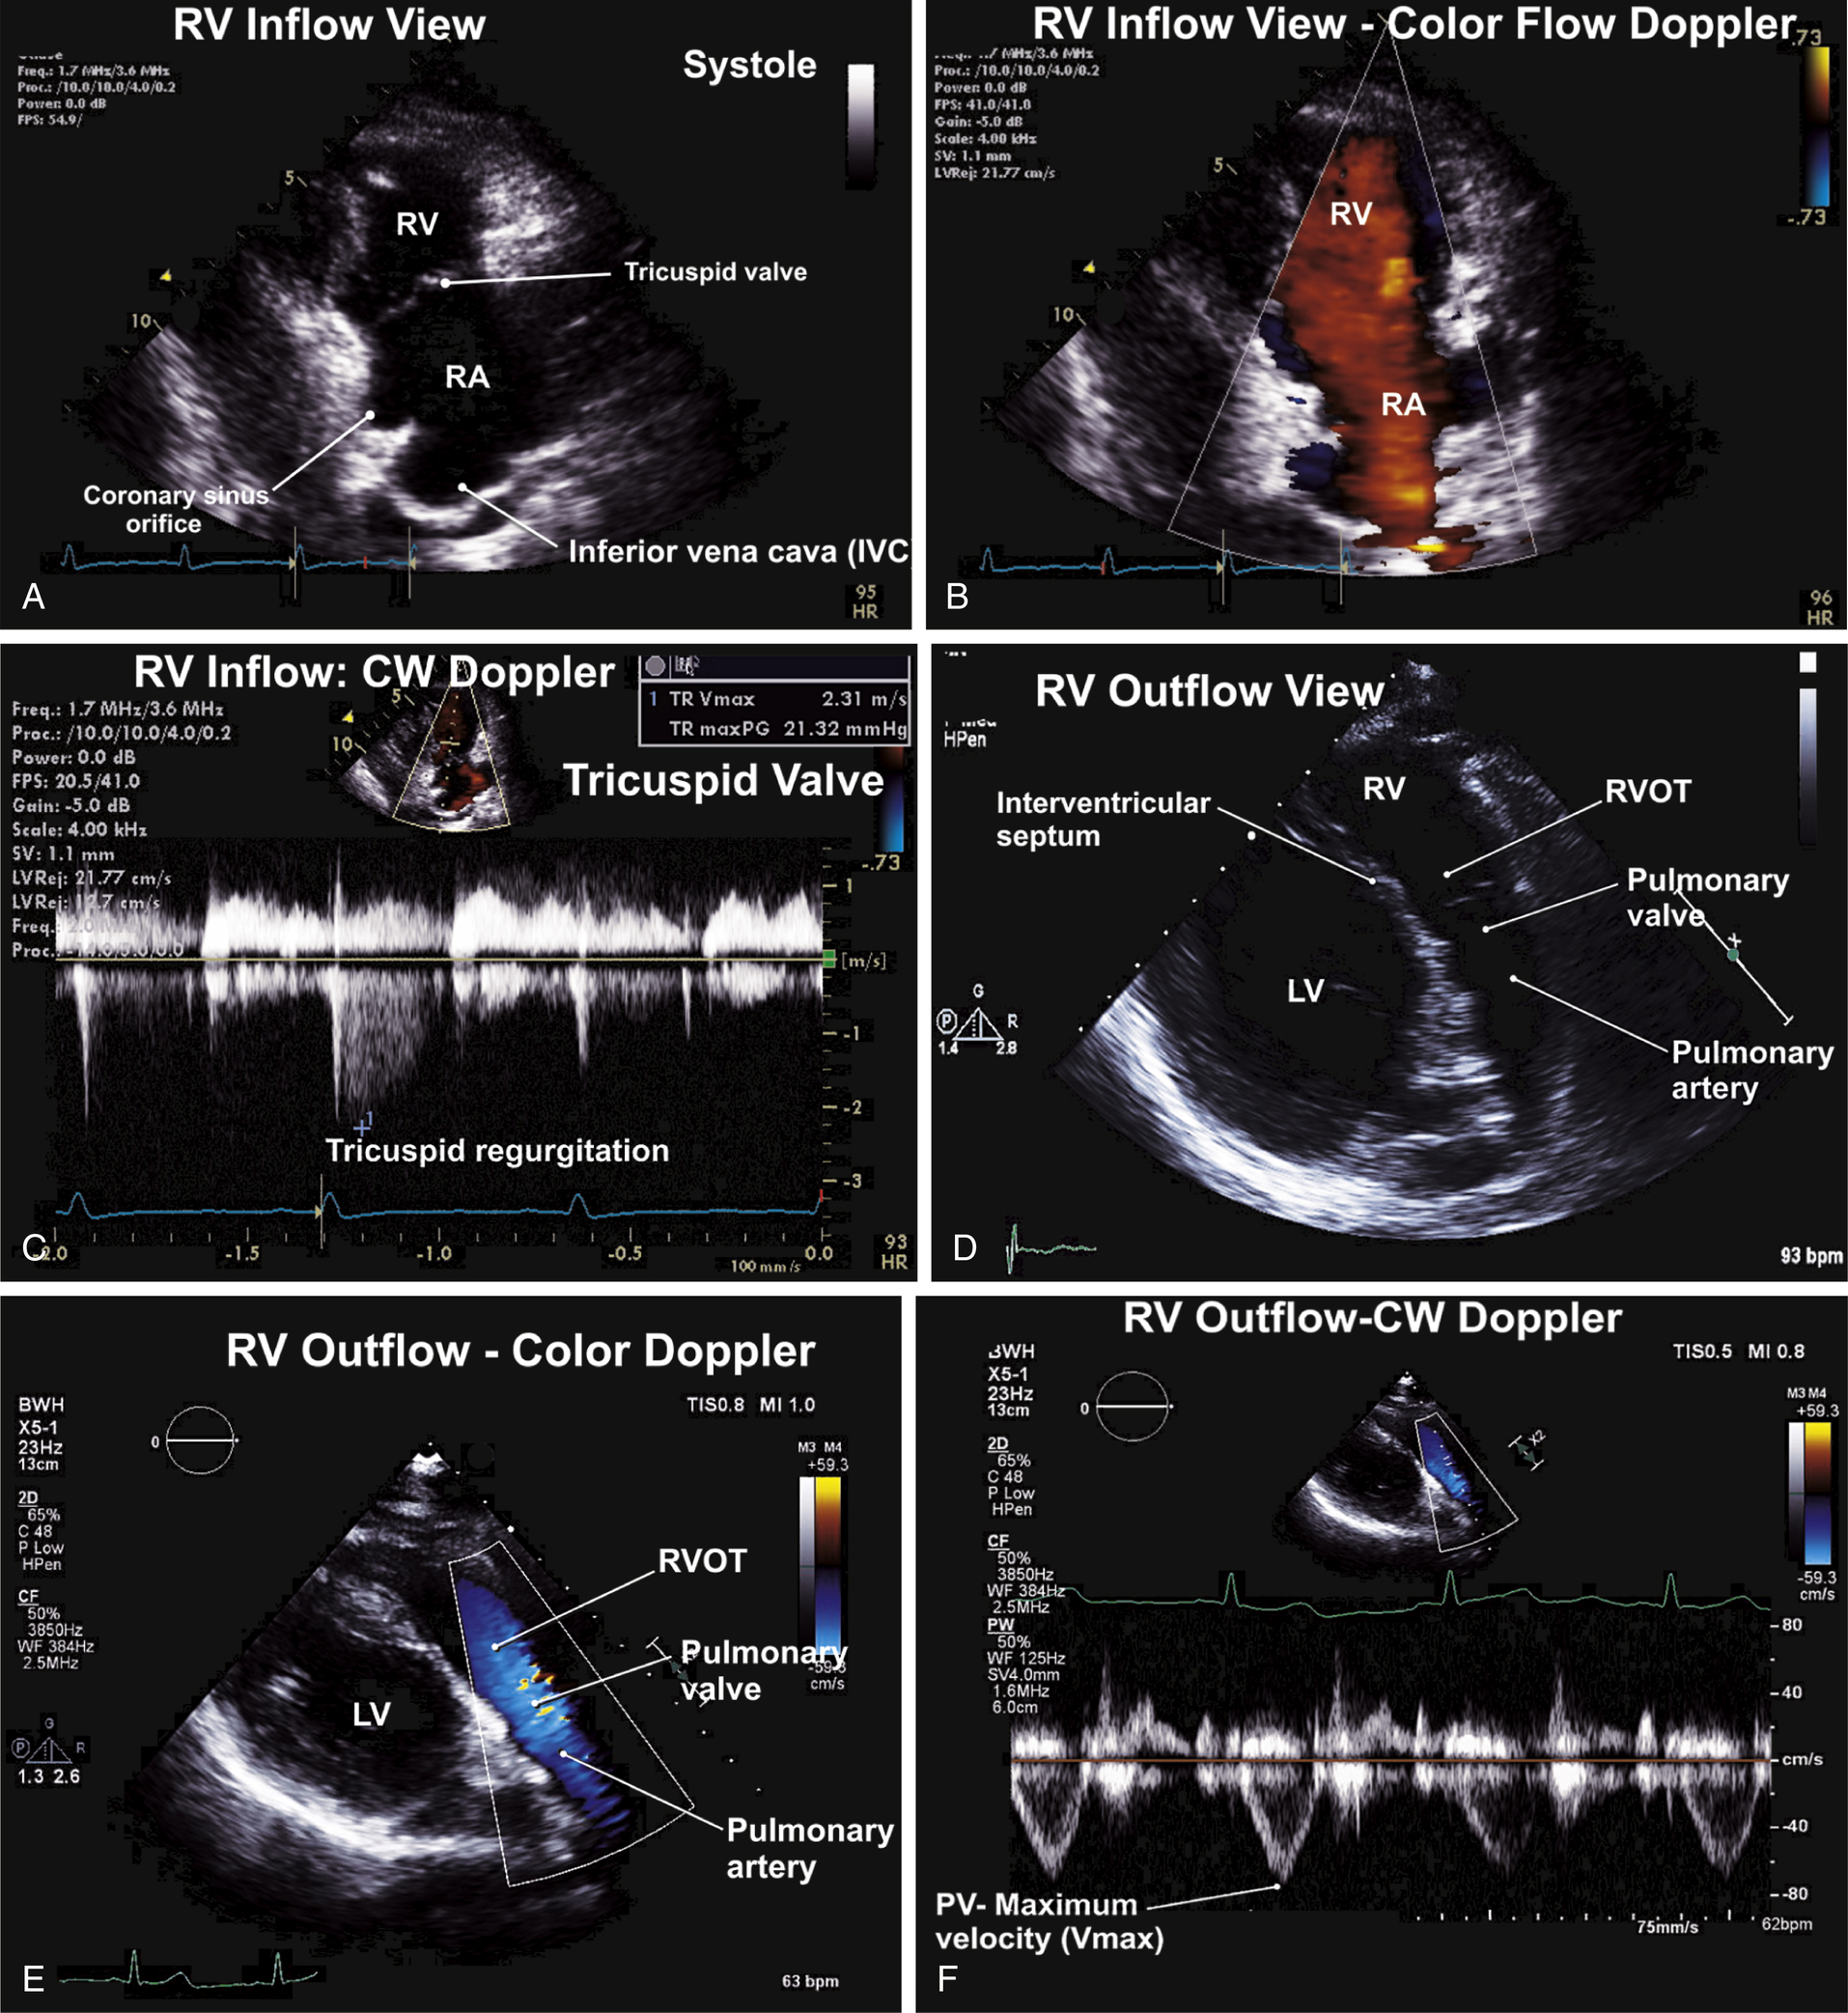

| Parasternal Views (see Figs. 9.1–9.4) | ||

| P | LAX | RV inflow, TV, RV, coronary sinus, IVC |

| P | LAX | RV outflow: RVOT, PV, PA |

Parasternal Long-Axis Views: Normal Examination (see Figs. 9.1 and 9.2)